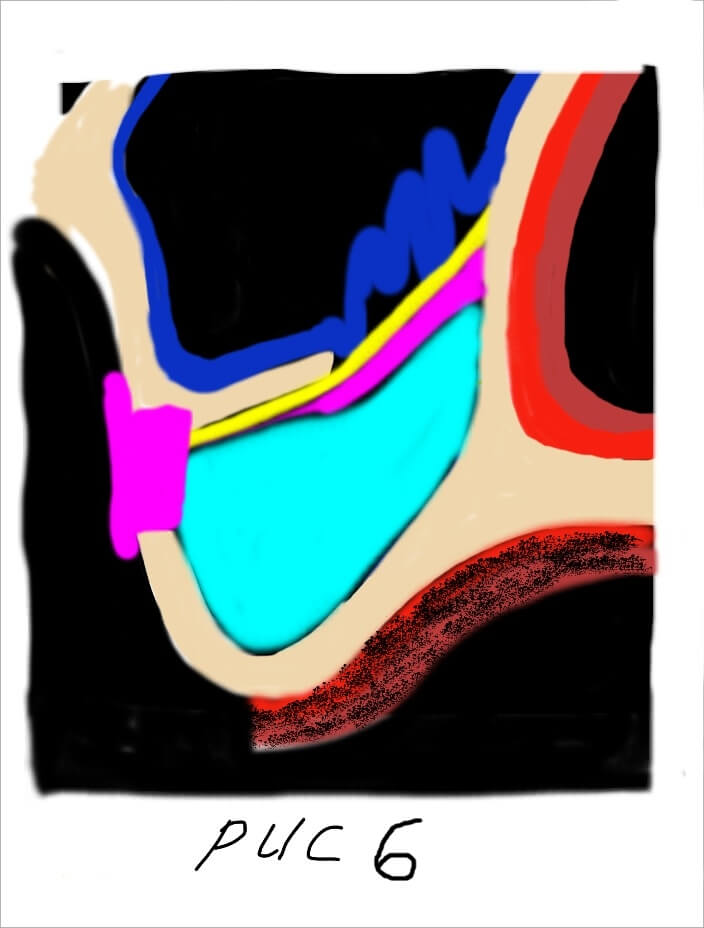

При этом, чем выше мы поднимаем слизистую пазухи тем больше кровоснабжения из соседних участков мы можем получить (рис 2).

При этом, чем выше мы поднимаем слизистую пазухи тем больше кровоснабжения из соседних участков мы можем получить (рис 2).  Сосудистая сеть наружной стенки носа многослойная и обильная. Следовательно, получить кровоснабжение из данного источника очень легко. Для этого необходимо как можно выше отсепарировать слизистую пазухи с носовой стенки. Благодаря этому мы получаем несколько плюсов. Во первых, напряжение слизистой уменьшается она становиться складчатой. Это предупреждает возникновение разрывов и трещин во время аугментации. Во вторых, мы получаем доступ к месту с обильным кровоснабжением которое крайне необходимо для последующего костеобразования и ремоделирования костной ткани.

Сосудистая сеть наружной стенки носа многослойная и обильная. Следовательно, получить кровоснабжение из данного источника очень легко. Для этого необходимо как можно выше отсепарировать слизистую пазухи с носовой стенки. Благодаря этому мы получаем несколько плюсов. Во первых, напряжение слизистой уменьшается она становиться складчатой. Это предупреждает возникновение разрывов и трещин во время аугментации. Во вторых, мы получаем доступ к месту с обильным кровоснабжением которое крайне необходимо для последующего костеобразования и ремоделирования костной ткани.